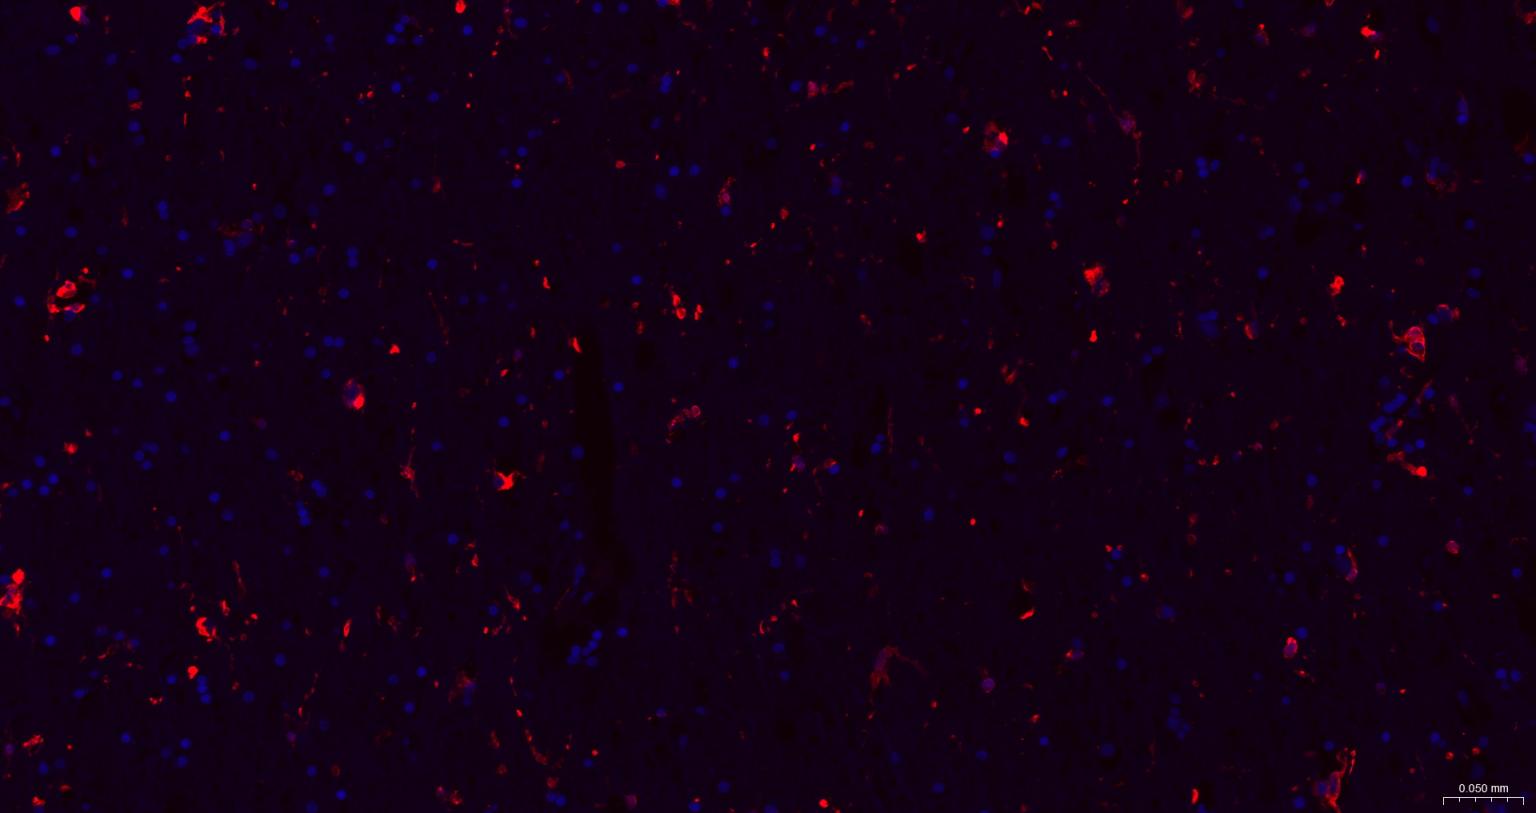

Paraformaldehyde-fixed, paraffin embedded Human Left Parietal Lobe; Antigen retrieval by boiling in sodium citrate buffer (pH6.0) for 15 min; The section was incubated with AIF1 / Iba1 Polyclonal Antibody, Unconjugated (bs-1363R) at 1:200 overnight at 4°C. Followed by conjugated Goat Anti-Rabbit IgG antibody (Red, bs-0295G-BF594), DAPI (blue, C02-04002) was used to stain the cell nuclei.